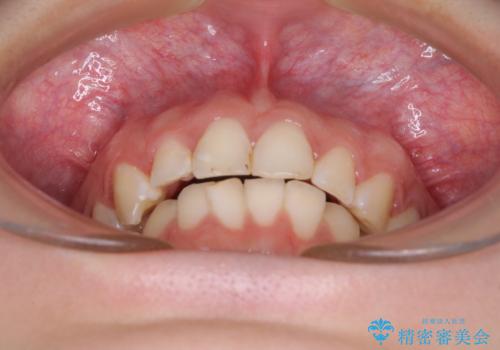

- 前歯の歯列不正を気にして来院された患者様です。

インビザラインでの矯正治療を希望されていましたが、奥歯の咬み合わせがインビザライン単独では改善困難と判断されたので、補助装置を併用することとしました。

まずは裏側の装置やワイヤー矯正を用いて歯列幅の狭い上顎を側方に拡大しつつ全体を後方に移動させ、その後インビザラインにて歯列を整えることとしました。